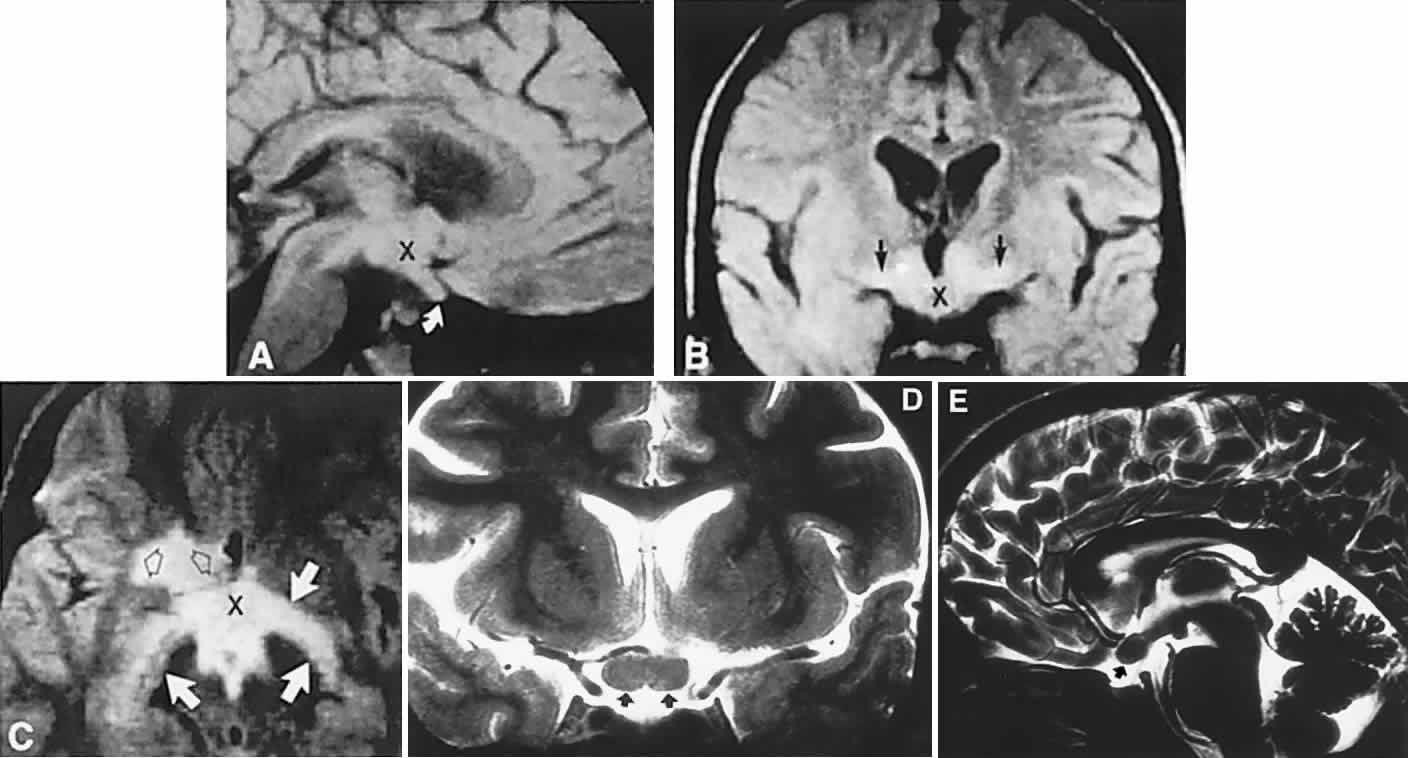

Fig. 2. Large prolactinoma. Original vision in the right eye (RE) was 8/200, left eye (LE) 1/200, with serum prolactin of 26,000 ng/ml and galactorrhea. Four months of bromocriptine reduced prolactin to 661 ng/ml, vision improved to RE 20/40, LE 20/50. At 3 years, vision was as follows: RE 20/30, LE 20/20; prolactin was 25.9 ng/ml. Enhanced magnetic resonance imaging. Sagittal (A) and coronal (C) images at diagnosis. Sagittal (B) and coronal (D) images at 2-year follow-up, showing dramatic shrinkage of the mass.

In previous decades, chiasmal interference with optic atrophy, but “normal” plain skull films, was referred to as “Cushing's syndrome of the chiasm,” caused by meningiomas, aneurysms, or other noncalcified suprasellar lesions. The modern neuroimaging techniques of enhanced CT, “bone-window” protocols, and gadolinium-contrasted MRI are now exceedingly sensitive in disclosing meningiomas or other parachiasmal masses (Fig. 4). At present, contrast-enhanced CT or MRI precisely demonstrate extra-axial tumor configuration; CT is superior in disclosing calcification or bone changes, but it is inferior for assessing suprasellar or intrasellar extension, postsurgical changes, and vascular displacement or encasement.76 Whether MRI or even MR angiography obviates standard selective arteriography, especially when surgical intervention is contemplated, is moot.

Fig. 4. Magnetic resonance imaging of a suprasellar meningioma (TR, 600 milliseconds; TE, 20 milliseconds). A. Coronal section of a large meningioma (large arrows), isodense to brain. B. Sagittal section. Note the normal sella and pituitary gland (p). Sagittal (C) and coronal (D) sections of a planum meningioma, extending into the sella. Note the upward deflection of the chiasm (arrow in C) and extension to the cavernous sinus (arrows in D).

CT scanning retains special relevance to craniopharyngioma diagnosis, currently superior to MRI in detection of calcification and cyst formation (Fig. 7A to C); however, the extent of involvement of adjacent structures, that is, the optic chiasm, third ventricle, and intracavernous carotid artery, is more clearly delineated by MRI (Fig. 7D and E).93 Craniopharyngioma fluid collections are found to be uniformly bright on T2-weighted sequences, but on T1-weighted images, the signal intensity may range from hypointense to hyperintense, reflecting the heterogeneous contents of cysts. Because calcification and cyst formation are hallmarks of craniopharyngiomas, CT is more specific than MRI. At times, intrinsic infiltration of tumor may thicken the chiasm and contiguous optic nerve, a radiologic configuration that mimics glioma.94 Likewise, glioma may be simulated when the optic canal is invaded and enlarged, but accompanying bony erosion of the sella weighs heavily toward craniopharyngioma.

Fig. 7. Computed tomography scan of a large, multicystic craniopharyngioma. A. Axial section through the sella shows destruction of the bony skull base. Axial (B) and coronal (C) sections show cysts (white arrows) and calcification (arrowheads). Contrast-enhanced magnetic resonance imaging of the craniopharyngioma. Sagittal (D) and coronal (E) sections with gadolinium show solid and cystic (arrows) portions.